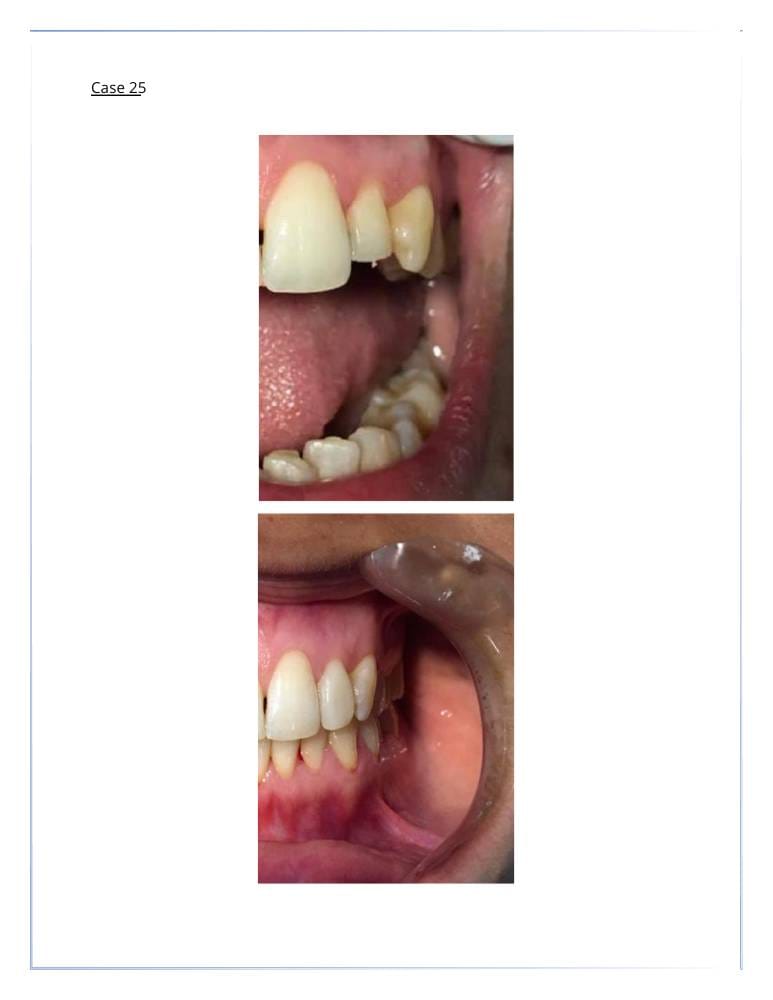

- التركيبات التجميلية لتعويض الأسنان المفقودة.

زراعة الأسنان

- استبدال الأسنان المفقودة بزراعات دائمة.

- توفير الدعم للتركيبات المتحركة أو الثابتة.

- خلع الاسنان والزراعه في نفس الجلسة.